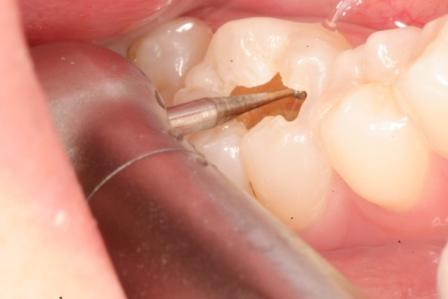

下顎7番の頬側歯茎部カリエスの原因 2025.06.04